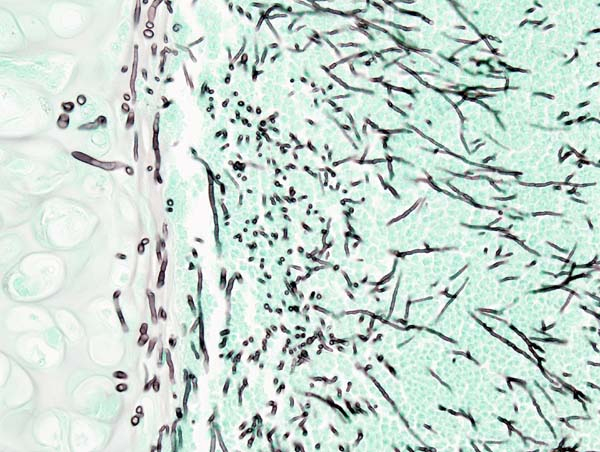

• 조직 절편에서는 다양한 형태로 관찰됨:

- 효묘형(yeast)

- 위균사(pseudohyphae): 위균사는 칸디다증의 진단적 단서로 작용하며, 특징적으로 싹튼 효모 세포들이 사슬 모양으로 연결되어 있으며 각 연결 부위는 constriction을 보임 → 진균사처럼 보이지만 실제로는 연속된 발아세포의 연결

- 산소 긴장도가 낮은 조건에서는 드물게 진균사(true hyphae)도 관찰됨

Candida Gram Stain, Wikipedia Commons